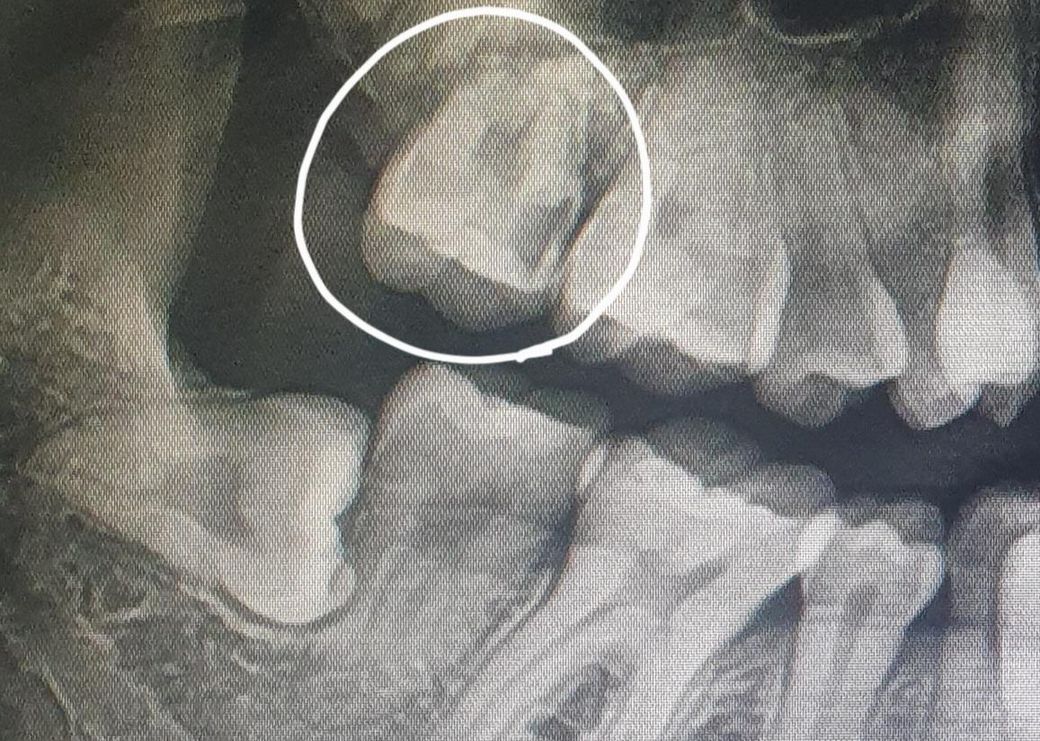

동그라미 친 치아 신경치료&크라운 해야할 정도인가요?

안녕하세요. 최근 스케일링 치료를 하러 갔다가 의사 선생님께서 해당 치아가 썩어서 신경치료를 해야한다고 합니다. 부모님께서는 신경치료하면 치아 다 버릴텐데 다른 병원에도 가보고 신경치료 외 치료를 할 수 있으면 그렇게 하라고 하십니다..(정확한 처치명을 모르겠습니다)

현재 통증은 없습니다만 신경치료를 무조건 해야하는 경우인지 궁금하여 문의남깁니다.

사진으로 봤을 경우에는 충치가 매우 깊게 생긴 것으로 보입니다. 충치를 제거했을 경우 신경의 노출이 딜 가능성이 높기 때문에 신경 치료를 해야 될 것으로 생각됩니다.

엑스레이 상으로 충치가 상당히 많이 진행된 상태 같습니다. 신경치료를 하시는게 좋을것같습니다.

현재 치아 정도로는 신경치료는 무조건 해야 합니다. 이미 충치가 상당히 진행되었다고 보시면 됩니다. 또한 충치 부위가 잇몸 아래로 너무 내려가거나 심하다면 발치까지도 할 수 있습니다. 통증이나 불편감이 없더라도 x-ray 상에서는 이미 상당히 많이 진행된 충치로 보여집니다.

해당 치아는 치아속 신경(치수)이 영향을 받았을 가능성이 꽤 높은정도로 파절 내지는 충치를 먹은 상태입니다 신경치료외 방법은 없습니다